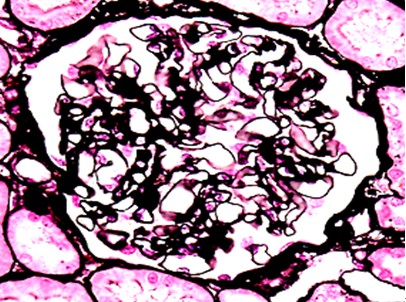

2.3 GS组织样本制备套液制作的石蜡切片,肾组织进行PAMS染色,胃粘膜组织行PAS组织化学染色,结果显示,肾小球基底膜和胃组织中的中性粘液染色清晰,色泽鲜艳,阳性物质定位准确,与传统方法制片染色效果相同(图4,5)。

图4 肾组织:肾小球基底膜呈黑色。PAMS×400